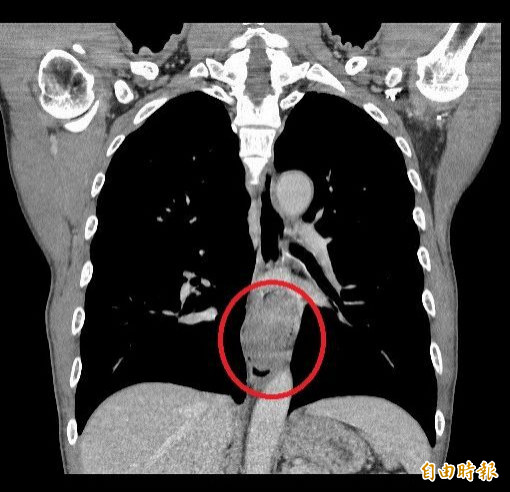

〔記者陳建志/台中報導〕58歲王姓男子長期抽菸喝酒,半年前發現吃飯會卡住,且胸口有灼熱感,原本以為只是年紀大或胃食道逆流,直到連喝水都吞不下去,胸口像被異物堵住,才趕緊就醫檢查,赫然發現已是下段食道癌第3期合併淋巴轉移,醫師建議新輔助放化療後,安排達文西手術切除食道,讓他有勇氣繼續抗癌。

劉柏毅表示,因患者腫瘤已8公分大,且轉移到腹部淋巴,經與討論後,建議先接受新輔助放射線治療及化學治療後,藉此縮小腫瘤並獲得穩定控制,接著再安排健保有補助的達文西食道切除暨胃管重建手術,這項微創手術是近年治療食道癌的重要突破,可在大幅減少傷口與疼痛的情況下,完成複雜的癌症切除。